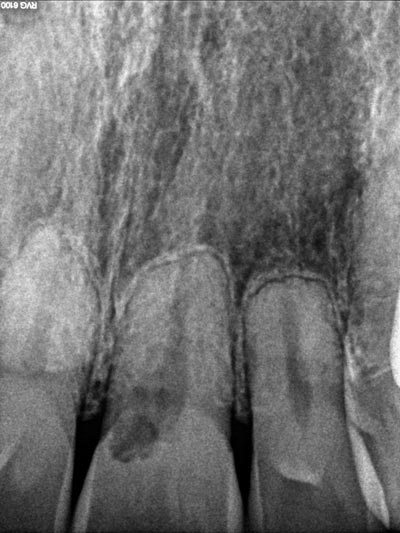

Imágenes: Endodoncia en un molar inferior izquierdo